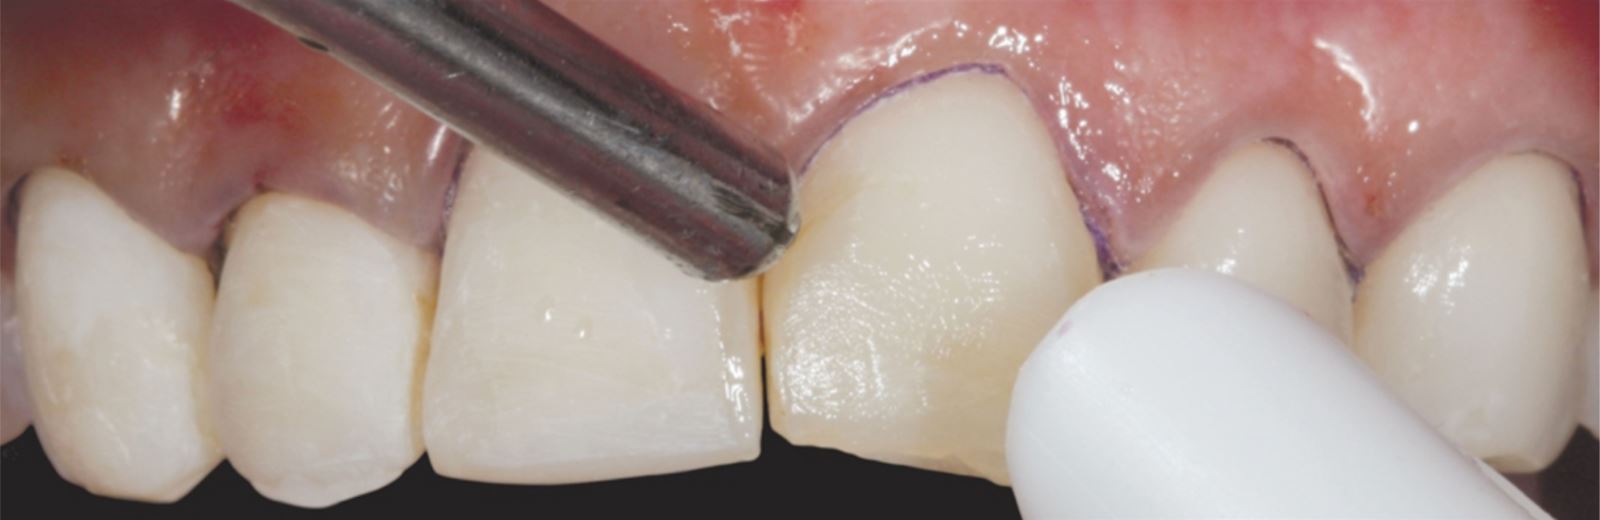

Príprava sulku:

Do gingiválneho sulku boli vložené pletené retrakčné vlákna Ultrapak™ veľkosti #0 na prípravu na leptanie.

Leptanie nepreparovanej skloviny:

Nepreparovaná sklovina bola leptaná 35% kyselinou fosforečnou Ultra-Etch po dobu 30 sekúnd.